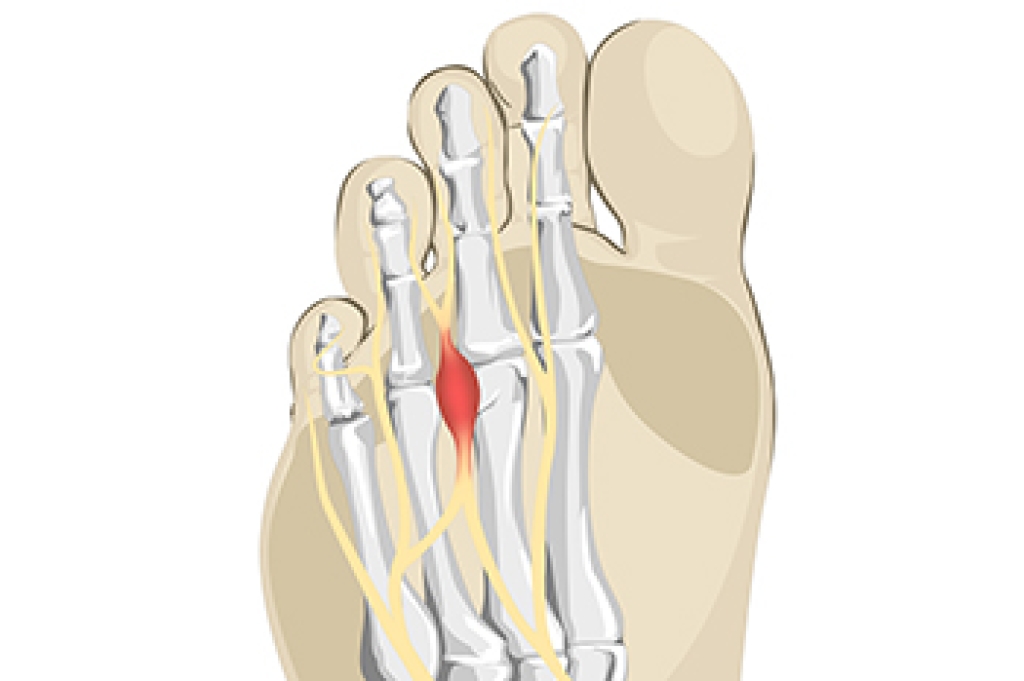

Cuboid syndrome is a common cause of lateral foot pain, which is pain on the outside of the foot. The condition may happen suddenly due to an ankle sprain, or it may develop slowly overtime from repetitive tension through the bone and surrounding structures.

- Repetitive Strain – Tension placed through the peroneus longus muscle from repetitive activities such as jumping and running may cause excessive traction on the bone causing it to sublux.